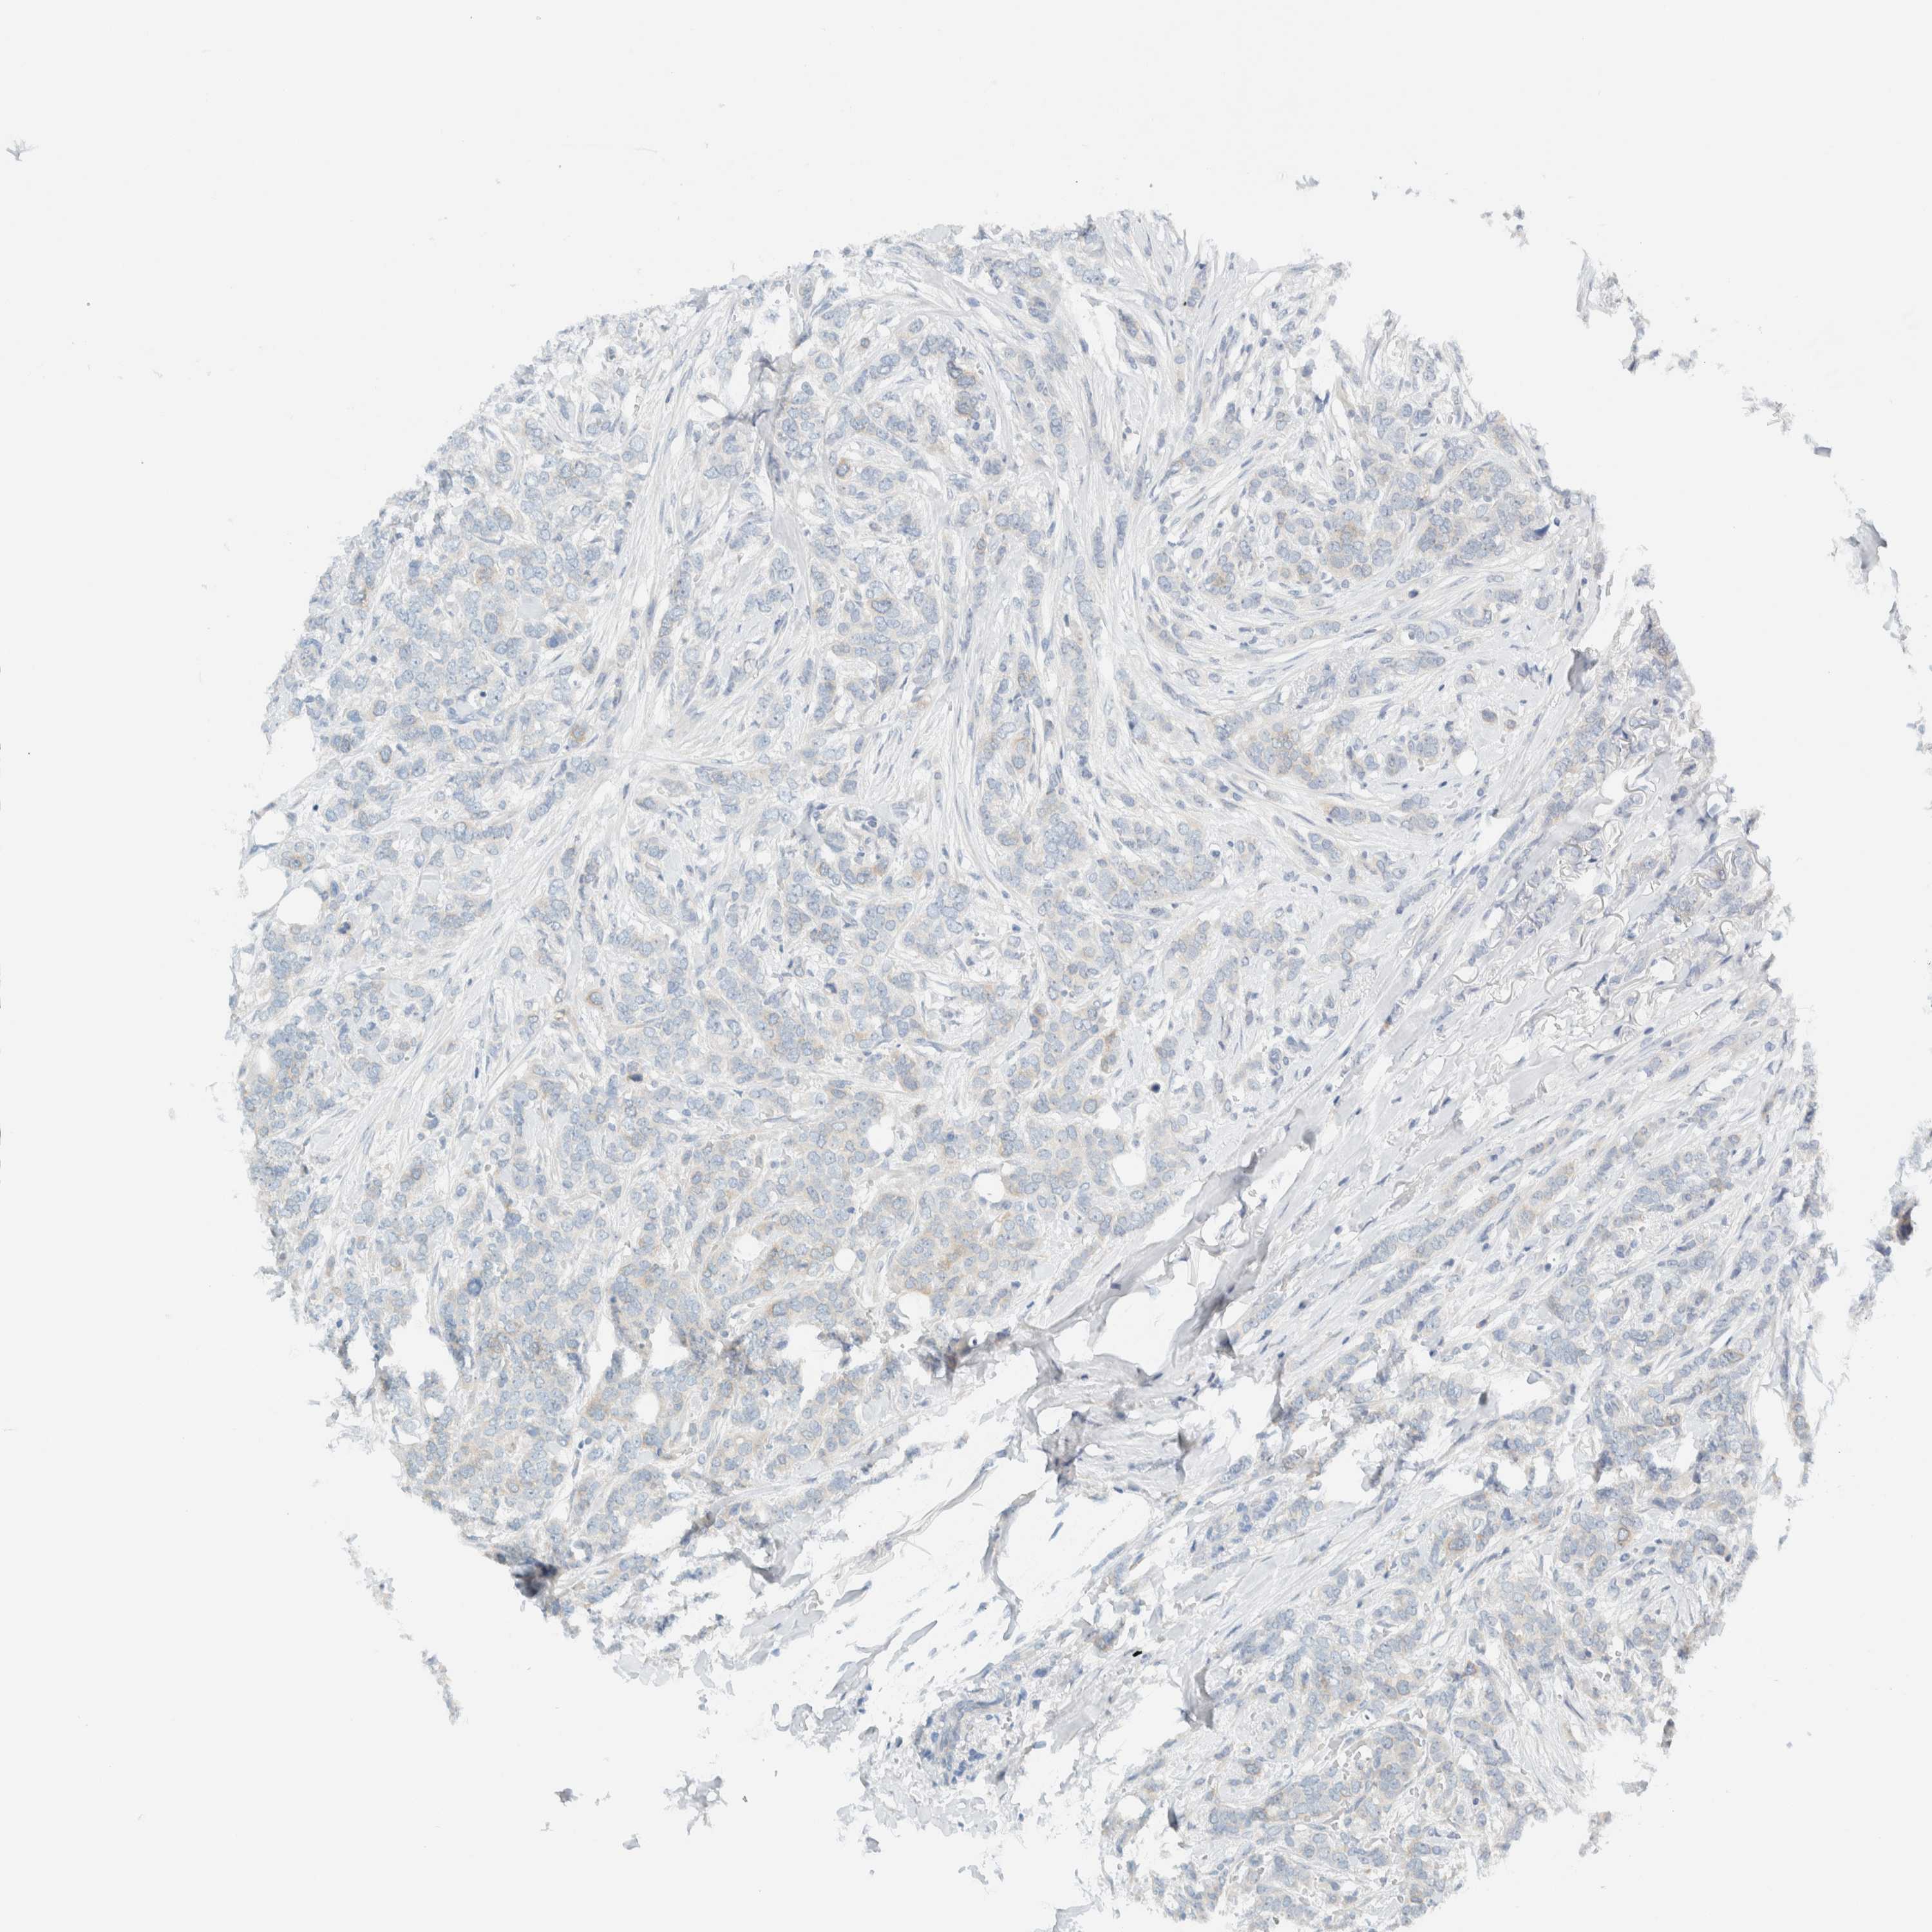

CANCER BREAST CANCER Show tissue menu

BRCA TCGA BRCA VALIDATION PROTEIN EXPRESSION